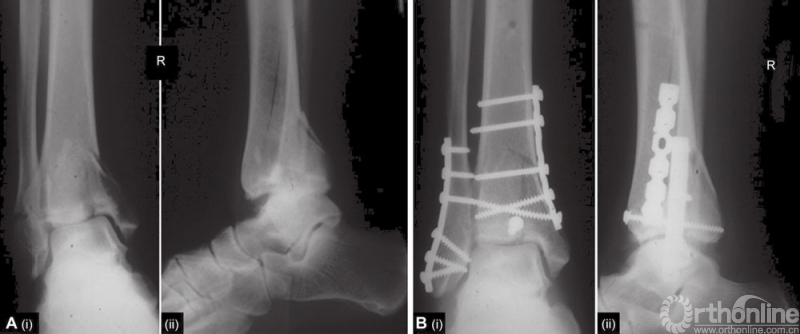

图1 Pilon粉碎的关节碎片,前方的碎片嵌入干骺端区域。骨折线延伸向骨干。前后联合韧带完好。腓骨有短的斜形骨折,稍有移位

图2 A~I Pilon骨折C型,标准正位与侧位X线摄影。冠状位CT平扫和3D重建。好的成像有利于入路决定和手术的准备